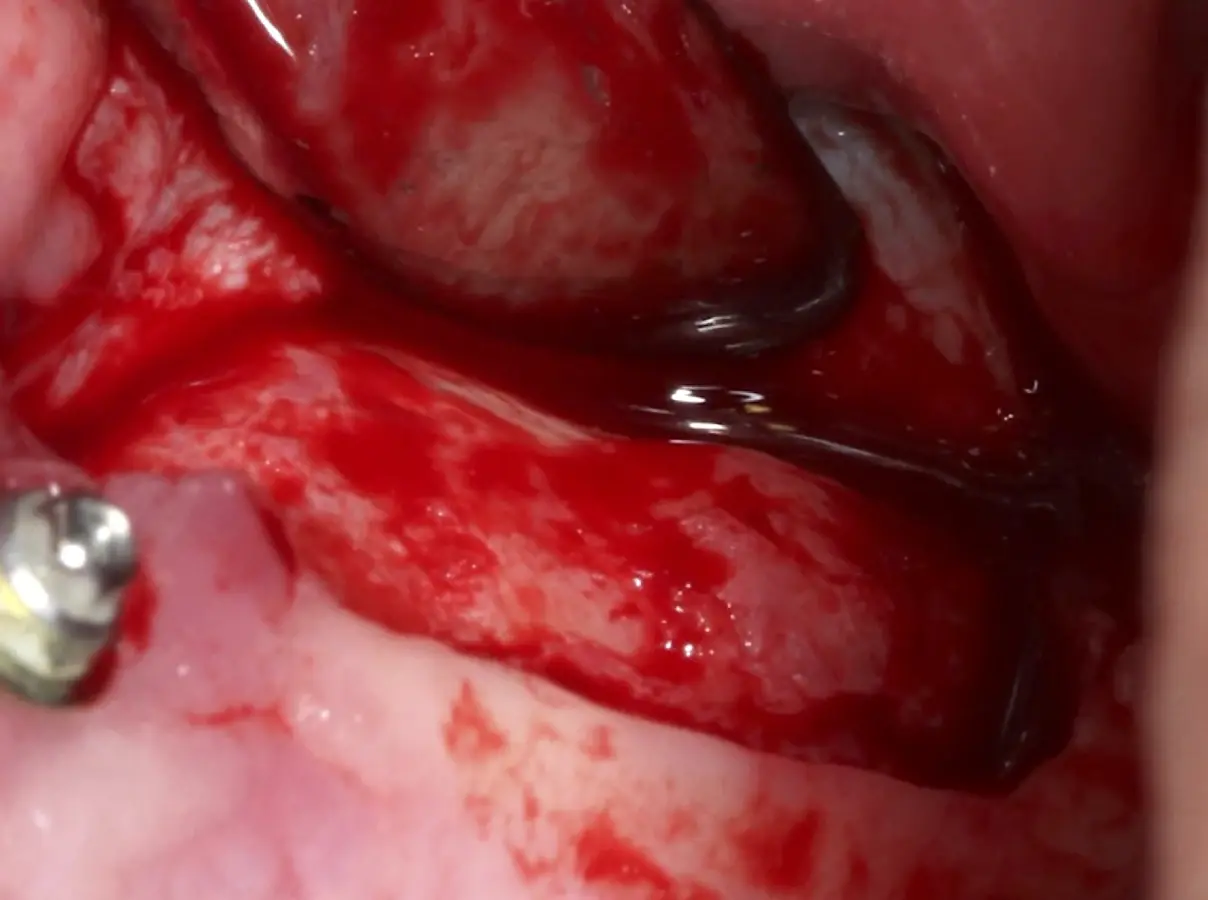

Una vez elevado el piso sinusal según la planificación se realiza la evaluación clínica de la integridad de la membrana y de posibles desgarros a través de la maniobra de Valsalva.24 Consiste en pedir al paciente que respire profundamente y retenga el aire, cerrar la boca, apretar la nariz con los dedos y forzar la salida de aire. Al final de la prueba, es necesario mantener la presión entre 10 a 15 segundos. Se identificará la movilidad de la membrana y la ausencia de burbujas de aire para corroborar que no hay perforaciones. Dependiendo de la decisión clínica se puede optar por adicionar en la superficie de la membrana de Schneider membranas de colágeno o de plasma rico en fibrina (PRF) para dar mayor soporte durante la inserción del biomaterial de relleno óseo (Figura 10).